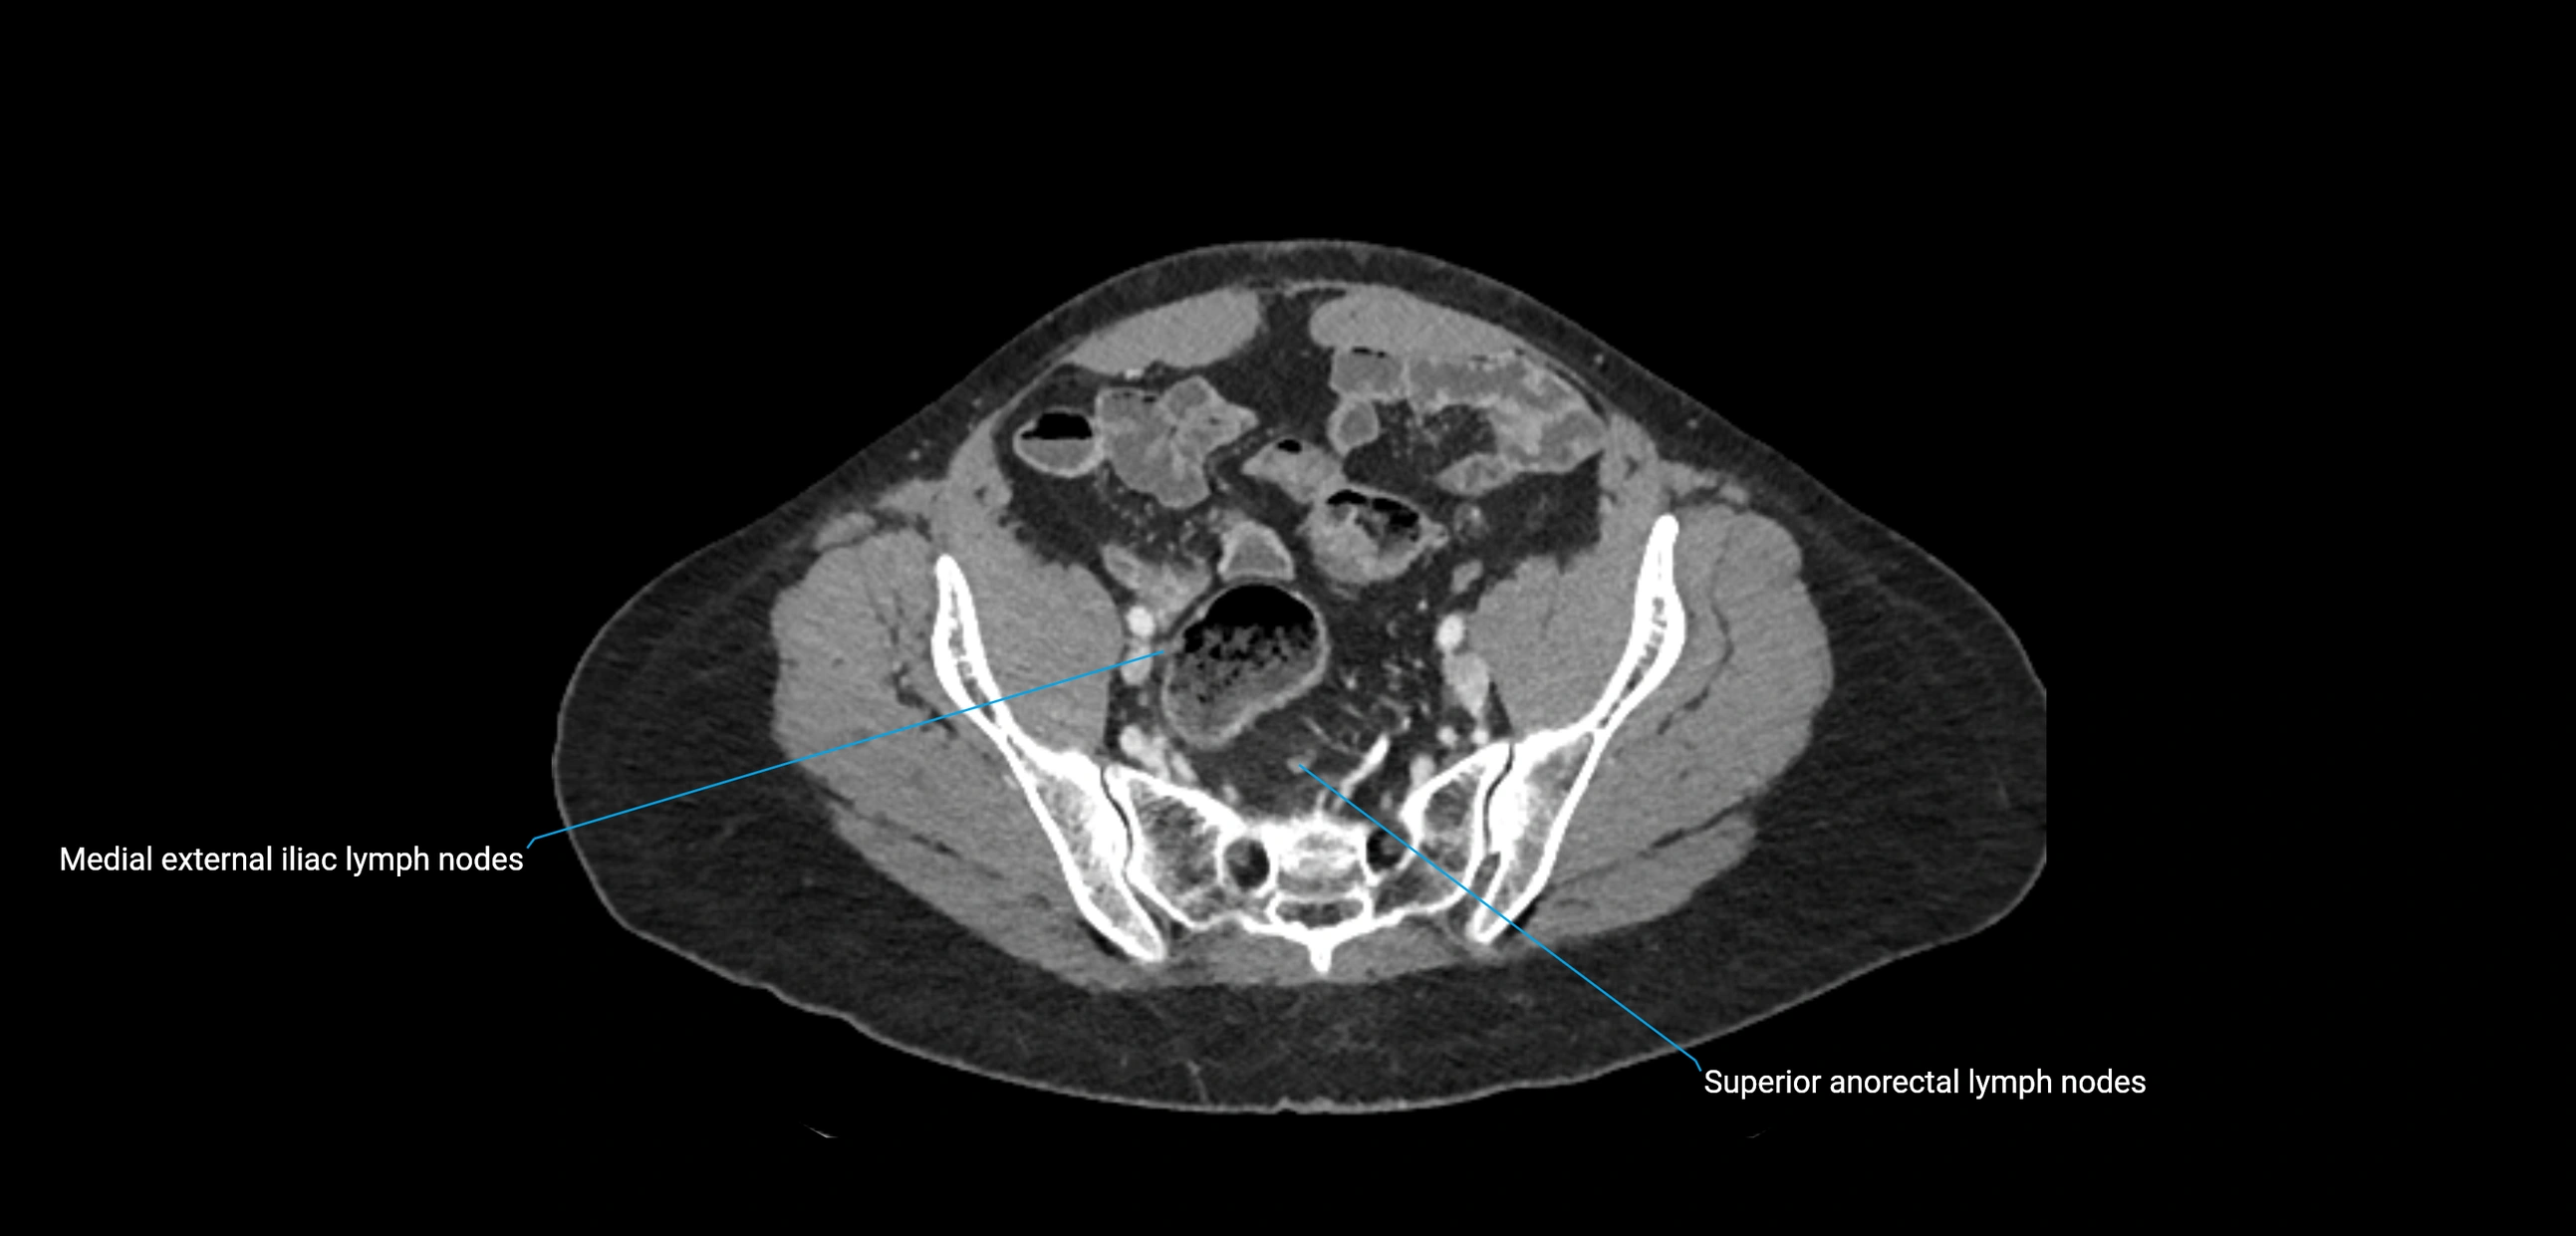

CT image

image